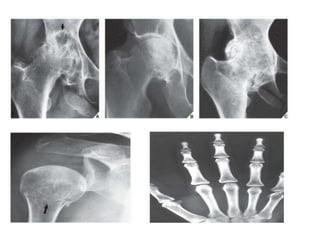

• ALINGMENT

• Assess the size of the

bones.

• Assess the number of

• Assess each bone for

normal shape and

contour; irregularities

can be from trauma,

congenital,

developmental or

pathological.

• Assess joint position:

trauma, inflammatory or

degenerative disease.

Anomalies of bone formation.

sacral agenesis (A), bilateral agenesis

of the fibulae (B), supernumerary

bones, polydactyly in both hands (C),

Polydactyly in the right foot (D).